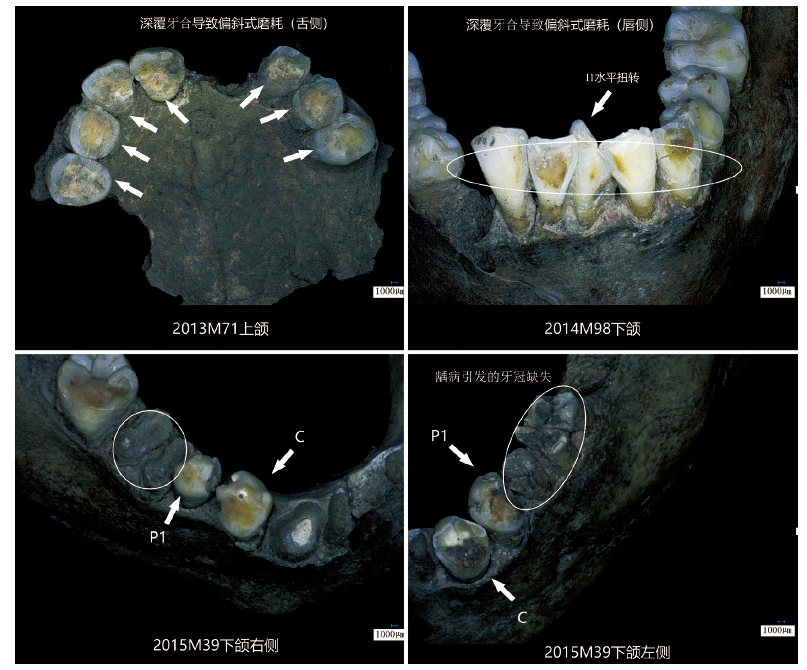

| 年龄组Age | 男性Male(n) | 女性Female(n) | 总计Total(n) |

| 青年组Youth | 1 | 2 | 3 |

| 壮年组Prime | 6 | 8 | 14 |

| 中年组Middle | 3 | 4 | 7 |

Tab.5 Relationship between deep overbite and age

Tab.6 The prevalence rate and the dental caries rate of obituary age

| 年龄组 Age | 患龋人数n of incidence | 总人数n of samples | 患龋牙数n of dental caries teeth | 总牙数n of teeth | 患龋率prevalence rate | 龋齿率dental caries rate |

| 未成年组Juvenile | 5 | 9 | 33 | 151 | 55.56% | 21.85% |

| 青年组Youth | 22 | 27 | 153 | 620 | 81.48% | 24.68% |

| 壮年组 Prime | 49 | 70 | 295 | 1673 | 70.00% | 17.63% |

| 中年组 Middle | 41 | 62 | 247 | 343 | 66.13% | 72.01% |

| 老年组 Old | 0 | 1 | 0 | 0 | 0.00% | 0.00% |

| 不详unknown | 3 | 5 | 20 | 29 | 60.00% | 68.97% |

| 总计 Total | 120 | 174 | 748 | 2816 | 68.97% | 26.56% |